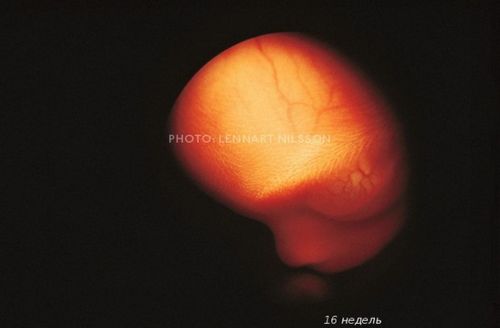

Відкрити завісу таємниці зміг шведський фотограф Леннарт Нільсон. Протягом 10 років він знімав, як розвивається ембріон від моменту зачаття і до народження. Подивитися його роботи ви можете нижче.

У 1965-му році Нільсон видав фотокнигу «A Child is Born», яка до сих пір залишається однією з найбільш продаваних.